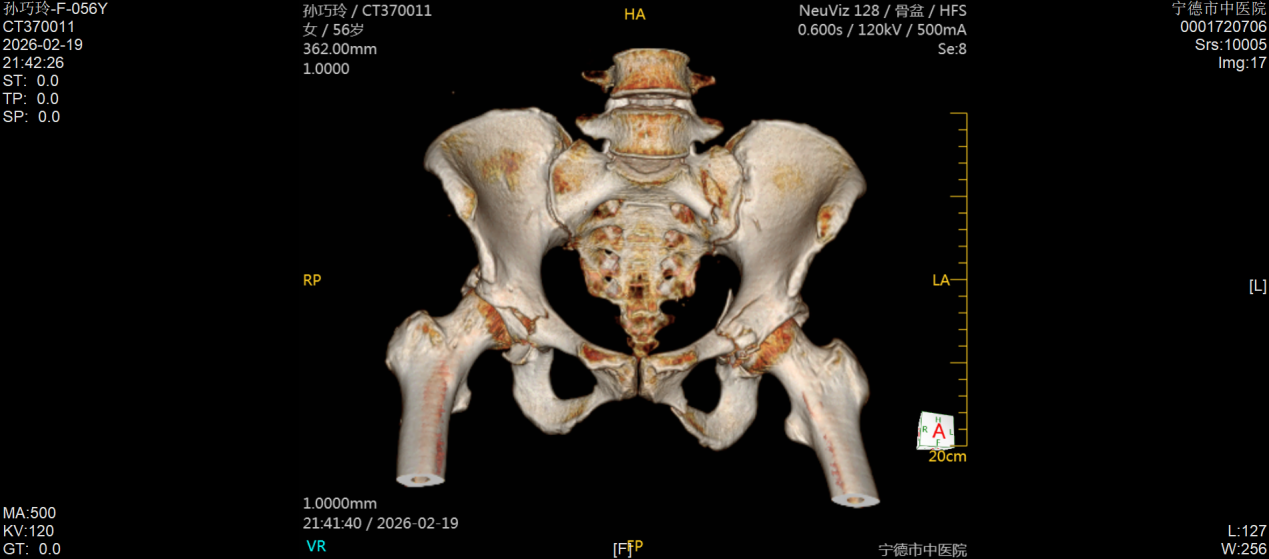

今年57岁的孙女士,因车祸外伤被紧急送往宁德市中医院创伤骨科就诊,经检查确诊为右侧髋臼后壁骨折伴股骨头后脱位,左侧髋臼T形骨折且累及四边体。据了解,髋臼骨折多由高能量损伤引发,其解剖结构复杂,毗邻重要血管神经,复位精度要求高、手术风险大,一直是创伤骨科领域的高难度手术,而双侧髋臼骨折更是该领域中极具挑战性的病例,不仅创伤重、术中出血风险高,诊疗难度也大幅提升。更为棘手的是,孙女士还合并有严重糖尿病及Ⅰ型呼吸衰竭,这无疑进一步增加了病情的复杂性和诊疗的艰巨性。

接诊后,该院创伤骨科主任黄聪第一时间牵头组建诊疗小组,面对复杂病情没有退缩,主动担当,迅速联合麻醉科、内分泌科、呼吸科等多个科室开展多学科联合诊疗(MDT),反复研讨患者病情,量身制定周密的诊疗方案。诊疗小组优先对孙女士的基础疾病进行干预,在短期内将其病情控制稳定,最终决定采用同期双侧手术方案,让患者仅需经历一次手术、一次麻醉,有效避免了二次手术带来的创伤,也显著减轻了患者的身体痛苦和经济负担。